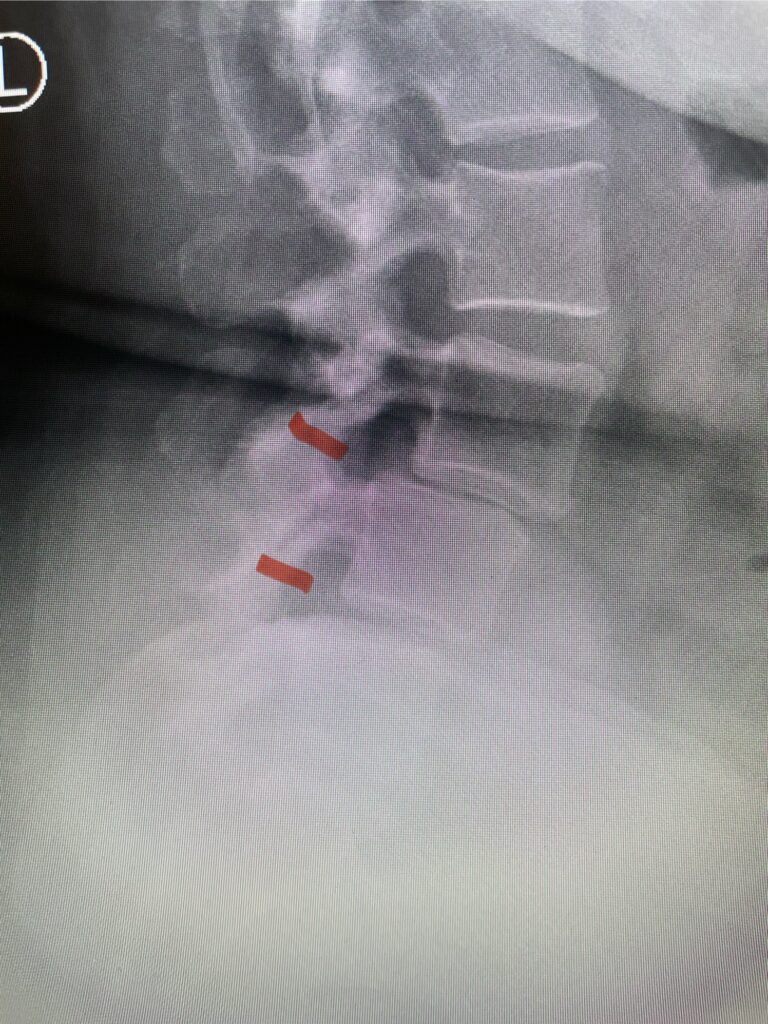

Here is a tough case: This is a 72 year-old male who presented with several months of progressive neck pain without symptoms of the arms or legs. […]